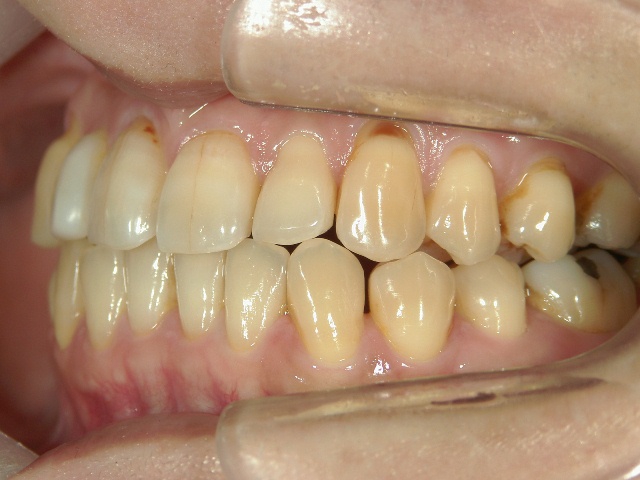

矯正歯科 治療前 正面

矯正歯科 治療前 左